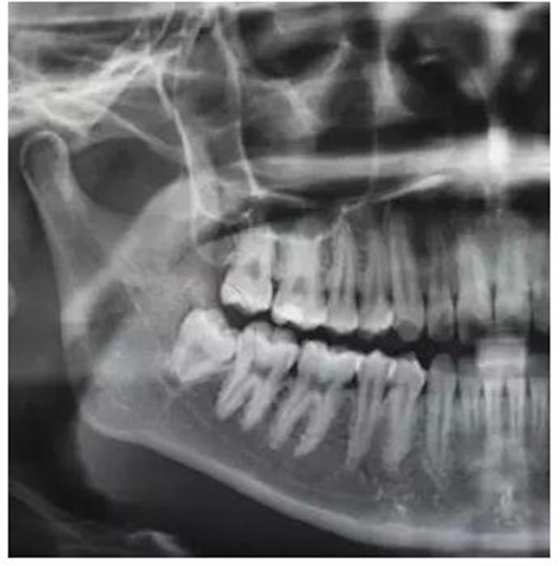

圖2.全景片局部放大影像:48融合根、牙根未發(fā)育完成,牙周膜清晰。

(1)根據(jù)全景片影像檢查:48牙冠合面平齊牙頸部,但牙根未完全發(fā)育完成,患者年紀(jì)尚小,屬于最佳拔牙年齡。故采用小切口,不附帶垂直切口

(5)該病例牙根呈錐形、牙根未發(fā)育完成、遠(yuǎn)中牙囊影比較明顯,故不用分牙,直接用挺拔除。